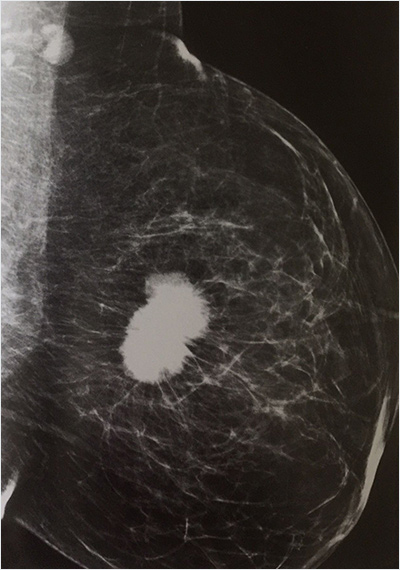

Mamografi, meme hastalıkları temel tanı yöntemidir. X ışınları yoluyla memenin görüntülenmesidir.

Meme kanserinin bazı türleri meme bez dokusu içinde kalsiyum birikimleri(kireçlenme-kalsifikasyon) ile görülü. Bunlar ele gelmez, kitle oluşturup elle ya da USG ile tespit edilmeden önce mamografi ile saptanır.

BI-RADS‘ Breast İmaging Reporting And Data Systems’ olarak ifade edilen meme raporlaması ve data kayıt sisteminin baş harflerinden oluşan raporlama yönteminin adıdır. Bu yöntem ile amaçlanan MG, meme US ve MR için raporlamada standart oluşturmak, yorumlamada karışıklığı azaltmak, sonuç takibini kolaylaştırmaktır.